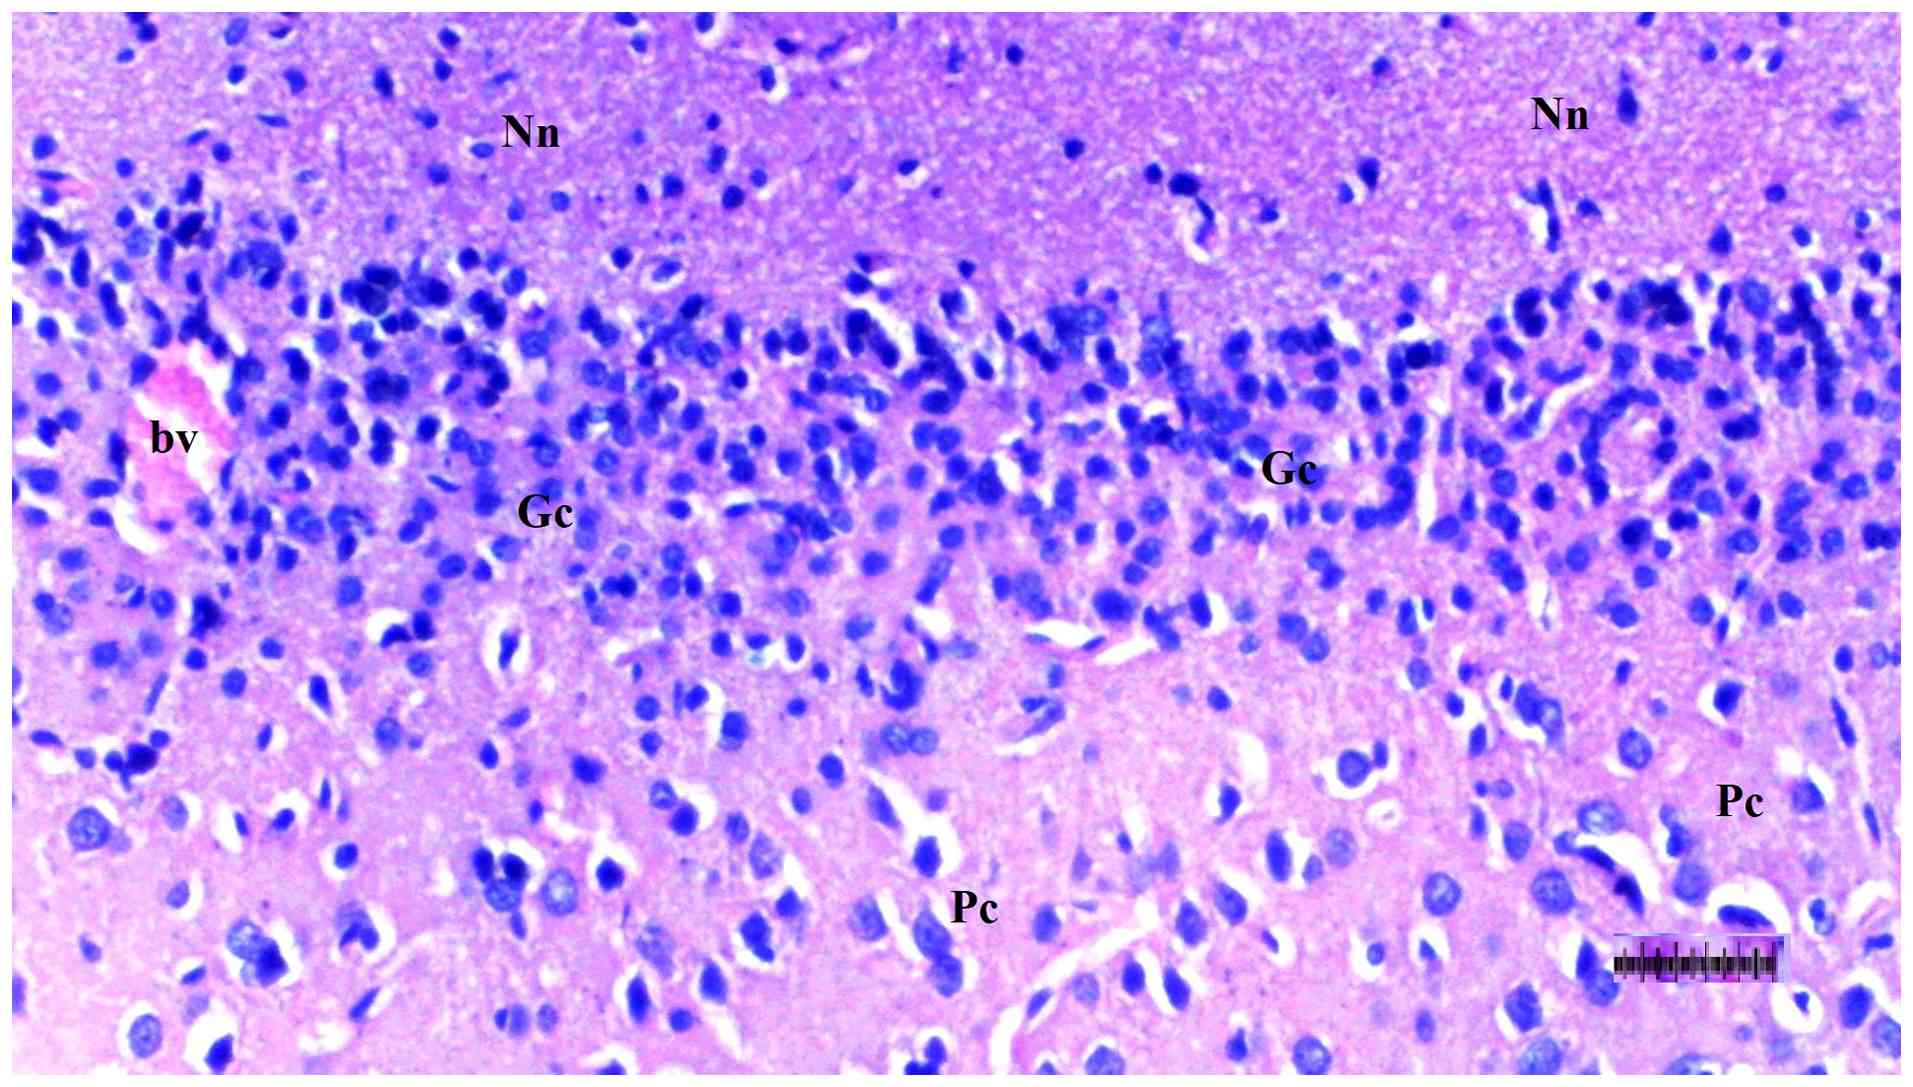

Representative light microscopy of

brain tissue from the diabetes + sepsis group. H&E staining.

Magnification, x100. Nn, neuroglia nuclei; Gc, fusiform cells; Pc,

pyramidal cells; bv, blood vessels.

Figure 11

Representative light microscopy of brain tissue from the diabetes + sepsis group. H&E staining. Magnification, x100. Nn, neuroglia nuclei; Gc, fusiform cells; Pc, pyramidal cells; bv, blood vessels.

Histopathological examination of brain tissue

An increase in cellularity (macrophages and astrocytes) was found to be significantly different among groups (P=0.014). The DM/SEP group showed a greater cellularity compared with the S and D groups (P<0.001 and P=0.003, respectively), while the FUL/C-60 group exhibited significantly lower cellularity (macrophages and astrocytes) compared with the DM/SEP group (P=0.034) (Table III; Fig. 9, Fig. 10, Fig. 11 and Fig. 12). Inflammation, both macrophagic and astroglial, was significantly different among groups (P=0.036), being significantly more pronounced in the DM/SEP group compared with the S group (P=0.003).